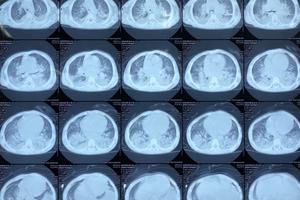

(Thanh tra) - Trước diễn biến phức tạp của tình hình dịch bệnh viêm phổi cấp do chủng vi rút mới Corona (nCoV) xâm nhập, chiều ngày 30/1, tại Hà Nội, Trung tâm Kiểm soát bệnh tật thành phố (Sở Y tế Hà Nội) đã tổ chức Hội nghị hướng dẫn giám sát và xử lý dịch bệnh nCoV.

(Thanh tra)- Thủ tướng Chính phủ vừa quyết định thành lập Ban Chỉ đạo Quốc gia phòng, chống dịch bệnh viêm đường hô hấp do chủng mới của vi rút Corona gây ra. Phó Thủ tướng Chính phủ Vũ Đức Đam làm Trưởng Ban Chỉ đạo.

Việt Nam đang được đánh giá là một trong những quốc gia trên thế giới ghi dấu ấn trong cuộc chiến chống lại bệnh viêm đường hô hấp do chủng mới của virus Corona (nCoV).